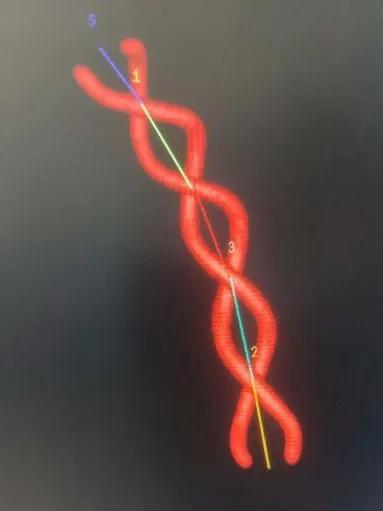

连接高压肝素盐水冲洗装置,6F导引导管在超滑导丝引导下超选进入左椎动脉入路段,行左椎动脉3D旋转造影并选取工作位,见左椎动脉V4段夹层动脉瘤,瘤颈约0.9cm,载瘤动脉约3.7mm(见下图)。

术中诊断:左侧椎动脉V4段夹层动脉瘤。

静脉肝素化,T-track支架导管微导丝导引下超选跨病变部位置入右侧大脑后动脉段。予以4.0×25mm Tubridge®血管重建装置于左椎动脉脊髓前动脉开口处近侧锚定缓慢释放,支架打开良好,贴壁完全。